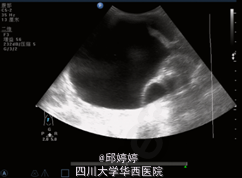

腹部膨隆,下腹部压痛,无肌紧张及反跳痛,余无特殊。超声检查:腹内查见巨大囊性团块,上至剑突下至盆腔,大小约11.5x12.5x9.2cm,边界清楚,形态较规则,内可见粗大条状分隔,内未见明显血流信号:腹腔内分隔囊性占位,性质?(图1,2)